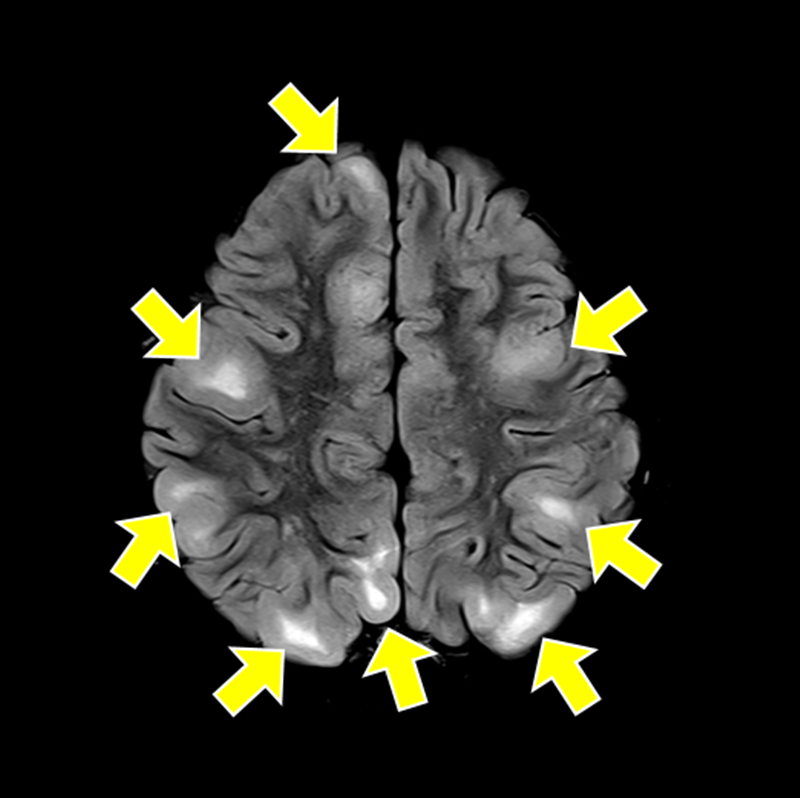

결절 경화증(tuberous sclerosis complex, TSC)은 종양억제유전자의 돌연변이로 인해 세포 증식이 조절되지 않고, 뇌·신장·피부·심장·폐 등 여러 장기에서 양성 종양이 발생하는 유전 희귀질환이다.

가장 흔한 증상인 뇌전증 발작과 피부의 혈관섬유종, 백반증을 비롯해 자폐스펙트럼장애, 인지장애, 신장 낭종, 폐세포 증식증 등 다양한 증상이 연령과 상관없이 나타나기 때문에 조기 진단과 장기적 관리가 필수적이다.

▲여러 장기에서 양성 종양이 발생하는 결절 경화증 환자의 뇌 MRI 검사 사진. 여러 개의 결절(노란색 화살표)이 관찰되고 있다.